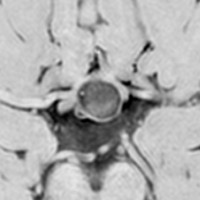

尿崩症で発症した小さな腫瘍

尿崩症で発症した9歳男児にみられたxanthogranuloma of the sellar resion。左はT1強調画像で高信号,右はT2強調画像で低信号であり,肉芽腫の特徴がみられます。のう胞部分はT2強調画像で,高信号になります(右図)。このような小さな頭蓋咽頭腫やラトケのう胞が尿崩症を呈することはまれですが,黄色肉芽腫の場合は小さくても症候性となることが多いです。神経下垂体組織が炎症性に破壊されるからと考えられます。